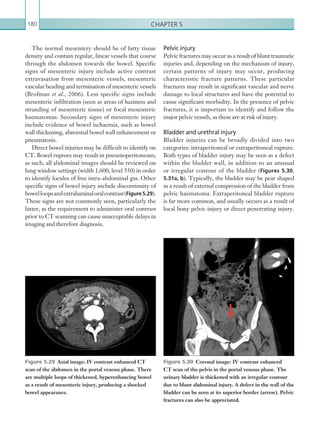

Calcification of a filling defect suggests chronicity.

Otherradiologicalsignsincludefillingdefectsthatcause

narrowing (as opposed to expansion), eccentric filling

defects that form an obtuse (as opposed to acute) angle

with the pulmonary artery wall and an abrupt artery

Figures 1.12a–c  Axial images: IV contrast enhanced

CT scans of the thorax in the arterial phase. Peripheral,

wedge-shaped area of consolidation shown. Over time,